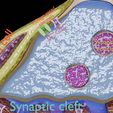

神经肌肉接头示意图

/https://fbi.cults3d.com/uploaders/27147996/illustration-file/c07beaf9-cb99-4252-8c6b-6384684af49a/aa-0001.jpg)